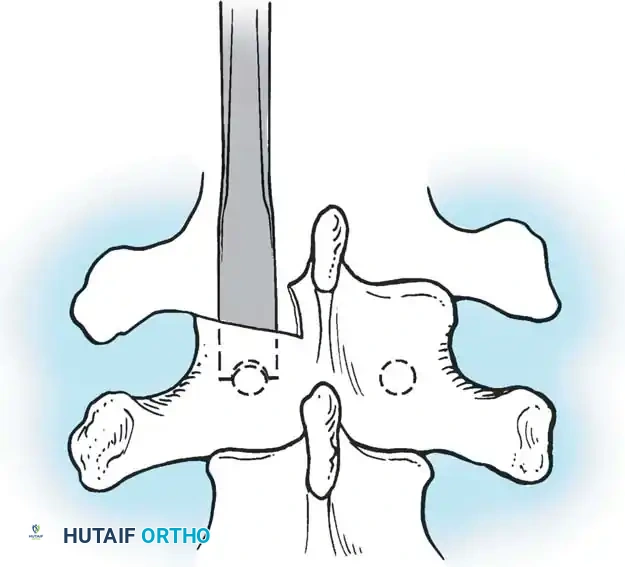

The Hall Technique

The Hall technique offers an alternative method for facet obliteration and grafting, particularly useful in rigid deformities.

Fig. 38-28: The Hall technique of facet fusion, involving sharp excision of the inferior facet and trough creation.

- Sharply amputate the inferior articular facet with a gouge and remove the bone fragment entirely. This exposes the cartilage of the superior facet.

- Remove the exposed cartilage completely with a sharp curet.

- Create a bleeding trough by removing the outer cortex of the superior facet.

- Impact cancellous bone grafts directly into this vascularized trough.

- Complete the procedure with global decortication of the posterior elements.